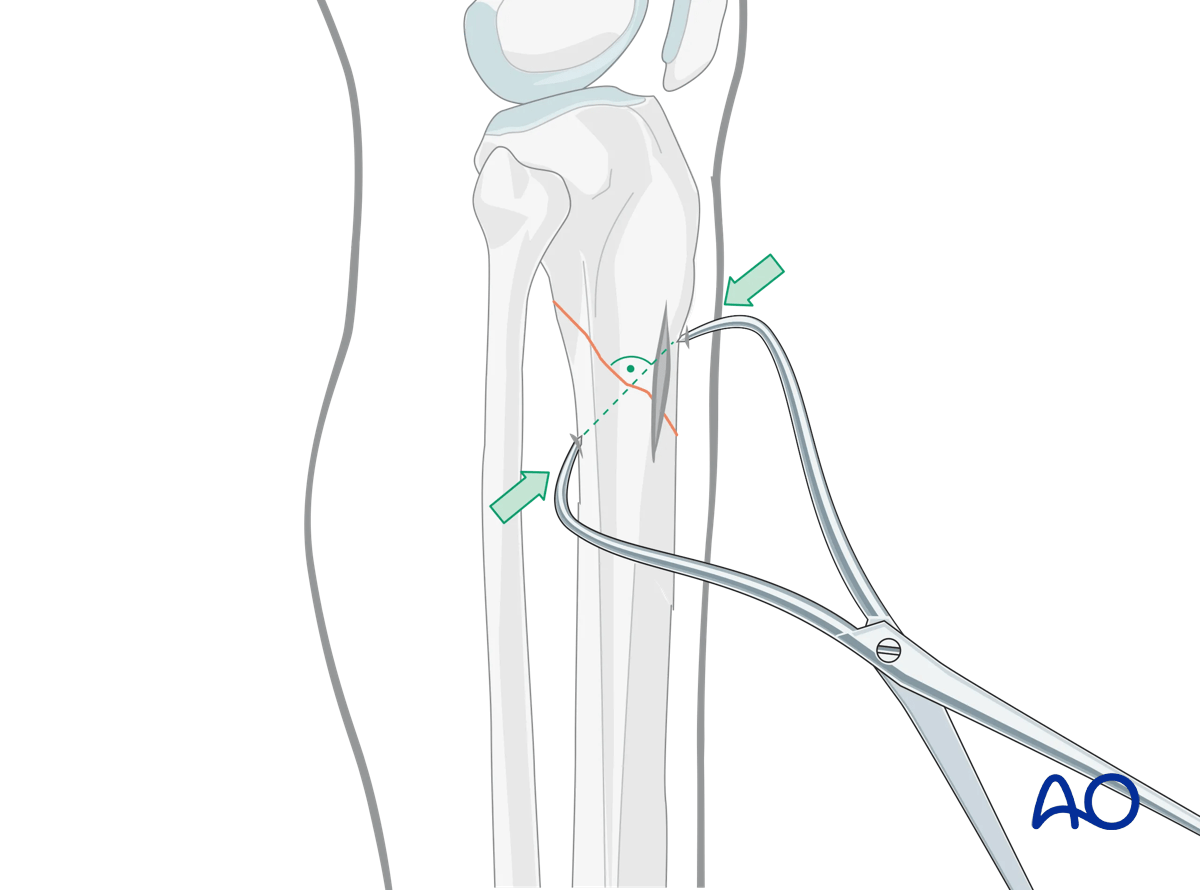

Percutaneous reduction forceps

Oblique or spiral fractures can often be reduced with pointed reduction forceps applied percutaneously.

Oblique fractures

If the fracture is oblique, a bone clamp, placed percutaneously, with its tips perpendicular to the fracture plane, can be used to compress the fracture surfaces. Together with some traction, this helps restore length as well as fracture apposition.